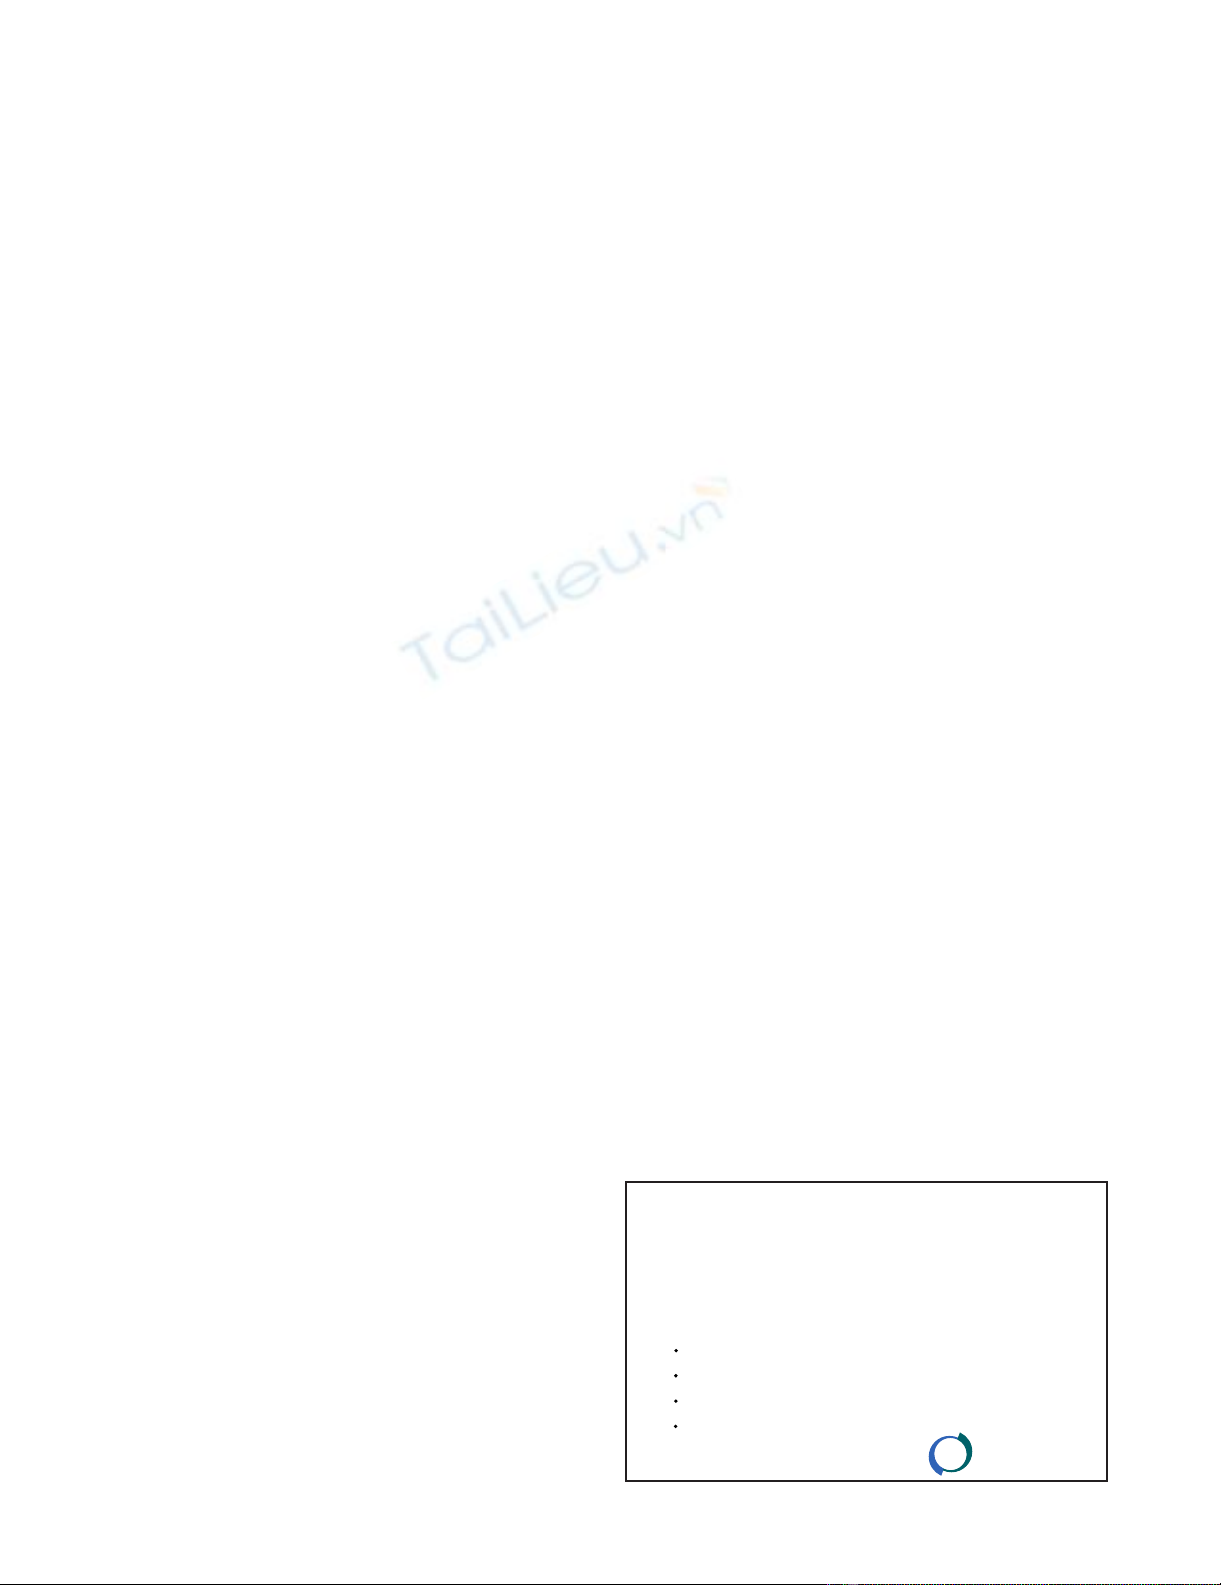

The proximal brachial and distal subclavian arteries were

ligated in continuity. Two interconnected Javid™ shunts

were inserted to carry blood flow from the subclavian to

the brachial artery in order to maintain perfusion (Fig. 3B)

during open reduction and internal fixation of the frac-

tured humerus, after which a subclavian to brachial

Supraclavicular exposure of the subclavian arteryFigure 3

Supraclavicular exposure of the subclavian artery. (A)

The phrenic nerve is retracted before the division of the sca-

lenus anterior muscle. (B) The subclavian artery is exposed

and ligated distally, with blood flow to the right arm being

maintained with the aid of a Javid shunt during open reduc-

tion and internal fixation of the fracture.

(A)

(B)